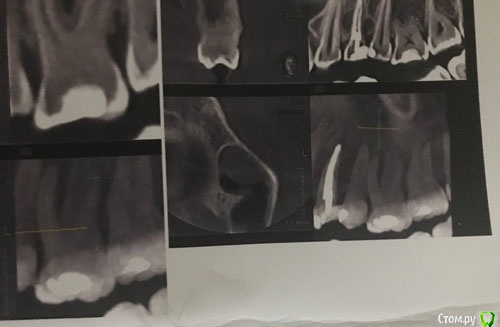

Ситуация такая: пару лет назад на десне появился свищ (24 зуб), мой лечащий врач сделала снимок (ничего не увидела), проколола свищ, приложила какую-то примочку с лекарством и рекомендовала полоскать и смотреть динамику. Года полтора я проходила то с появляющимся, то со вновь исчезающим свищом. После посещения другого врача выяснилось, что внутри установлен штифт, и все-таки есть какие-то проблемы в корне, но по снимку было непонятно - то-ли кариес корня, то-ли механическое повреждение. Но исходя из локализации воспаления, было показано удаление зуба с последующим протезированием. На тот момент я кормила грудью, с удалением решила повременить. И через пол-года случилось воспаление десны с острой болью на фоне сниженного иммунитета из-за простуды. В срочном порядке обратилась к третьему специалисту, - мой зуб был распломбирован, установлена временная пломба. Врач дал направление на кт.

Цитирую описание: "зуб депульпирован. Коронковая часть восстановлена пломбой. Щечный канал зуба запломбирован до апекса. В небный канал установлен штифт до 1/2 длины корня, далее канал зуба запломбирован, не доходя до апекса на 2.0мм, материал доведен до мезиальной поверхности апикальной трети корня. Периодонтальное пространство в области апекса корня зуба не расширено. В области средней трети корня зуба с мезиальной стороны определяется дестркуция костной ткани овоидной формы, однородной структуры, размерами до 3.1х5.4х7.4мм (ШхВхГ), с ровными четкими контурами. Определяется дефект щечной кортикальной пластинки челюсти в области очага. Заключение: Хронический периодонтит. Периодонтно-парадонтальное поражение зуба. Объемное образование левого верхнечелюстного синуса, дифференцровать с ретенционной кистой."

Врач сказал, что зуб безнадежен, признаки перелома корня на лицо.